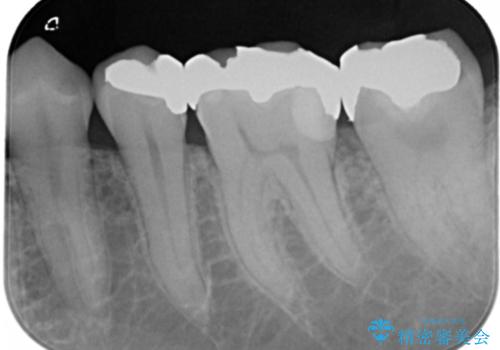

- 左下6番の銀歯が不適であったためやり変えを勧めたところセラミックでの治療を希望された患者様です。

切削量などを考慮し、フルジルコニアクラウンでの治療を選択しました。

う蝕が歯髄に近接していたので麻酔が切れた後に痛みなどの症状が出る可能性をお伝えしています。

う蝕が深く切削量が多くなりましたが痛みなどは起きなかったので、予定通りフルジルコニアクラウンでの治療で進めました。